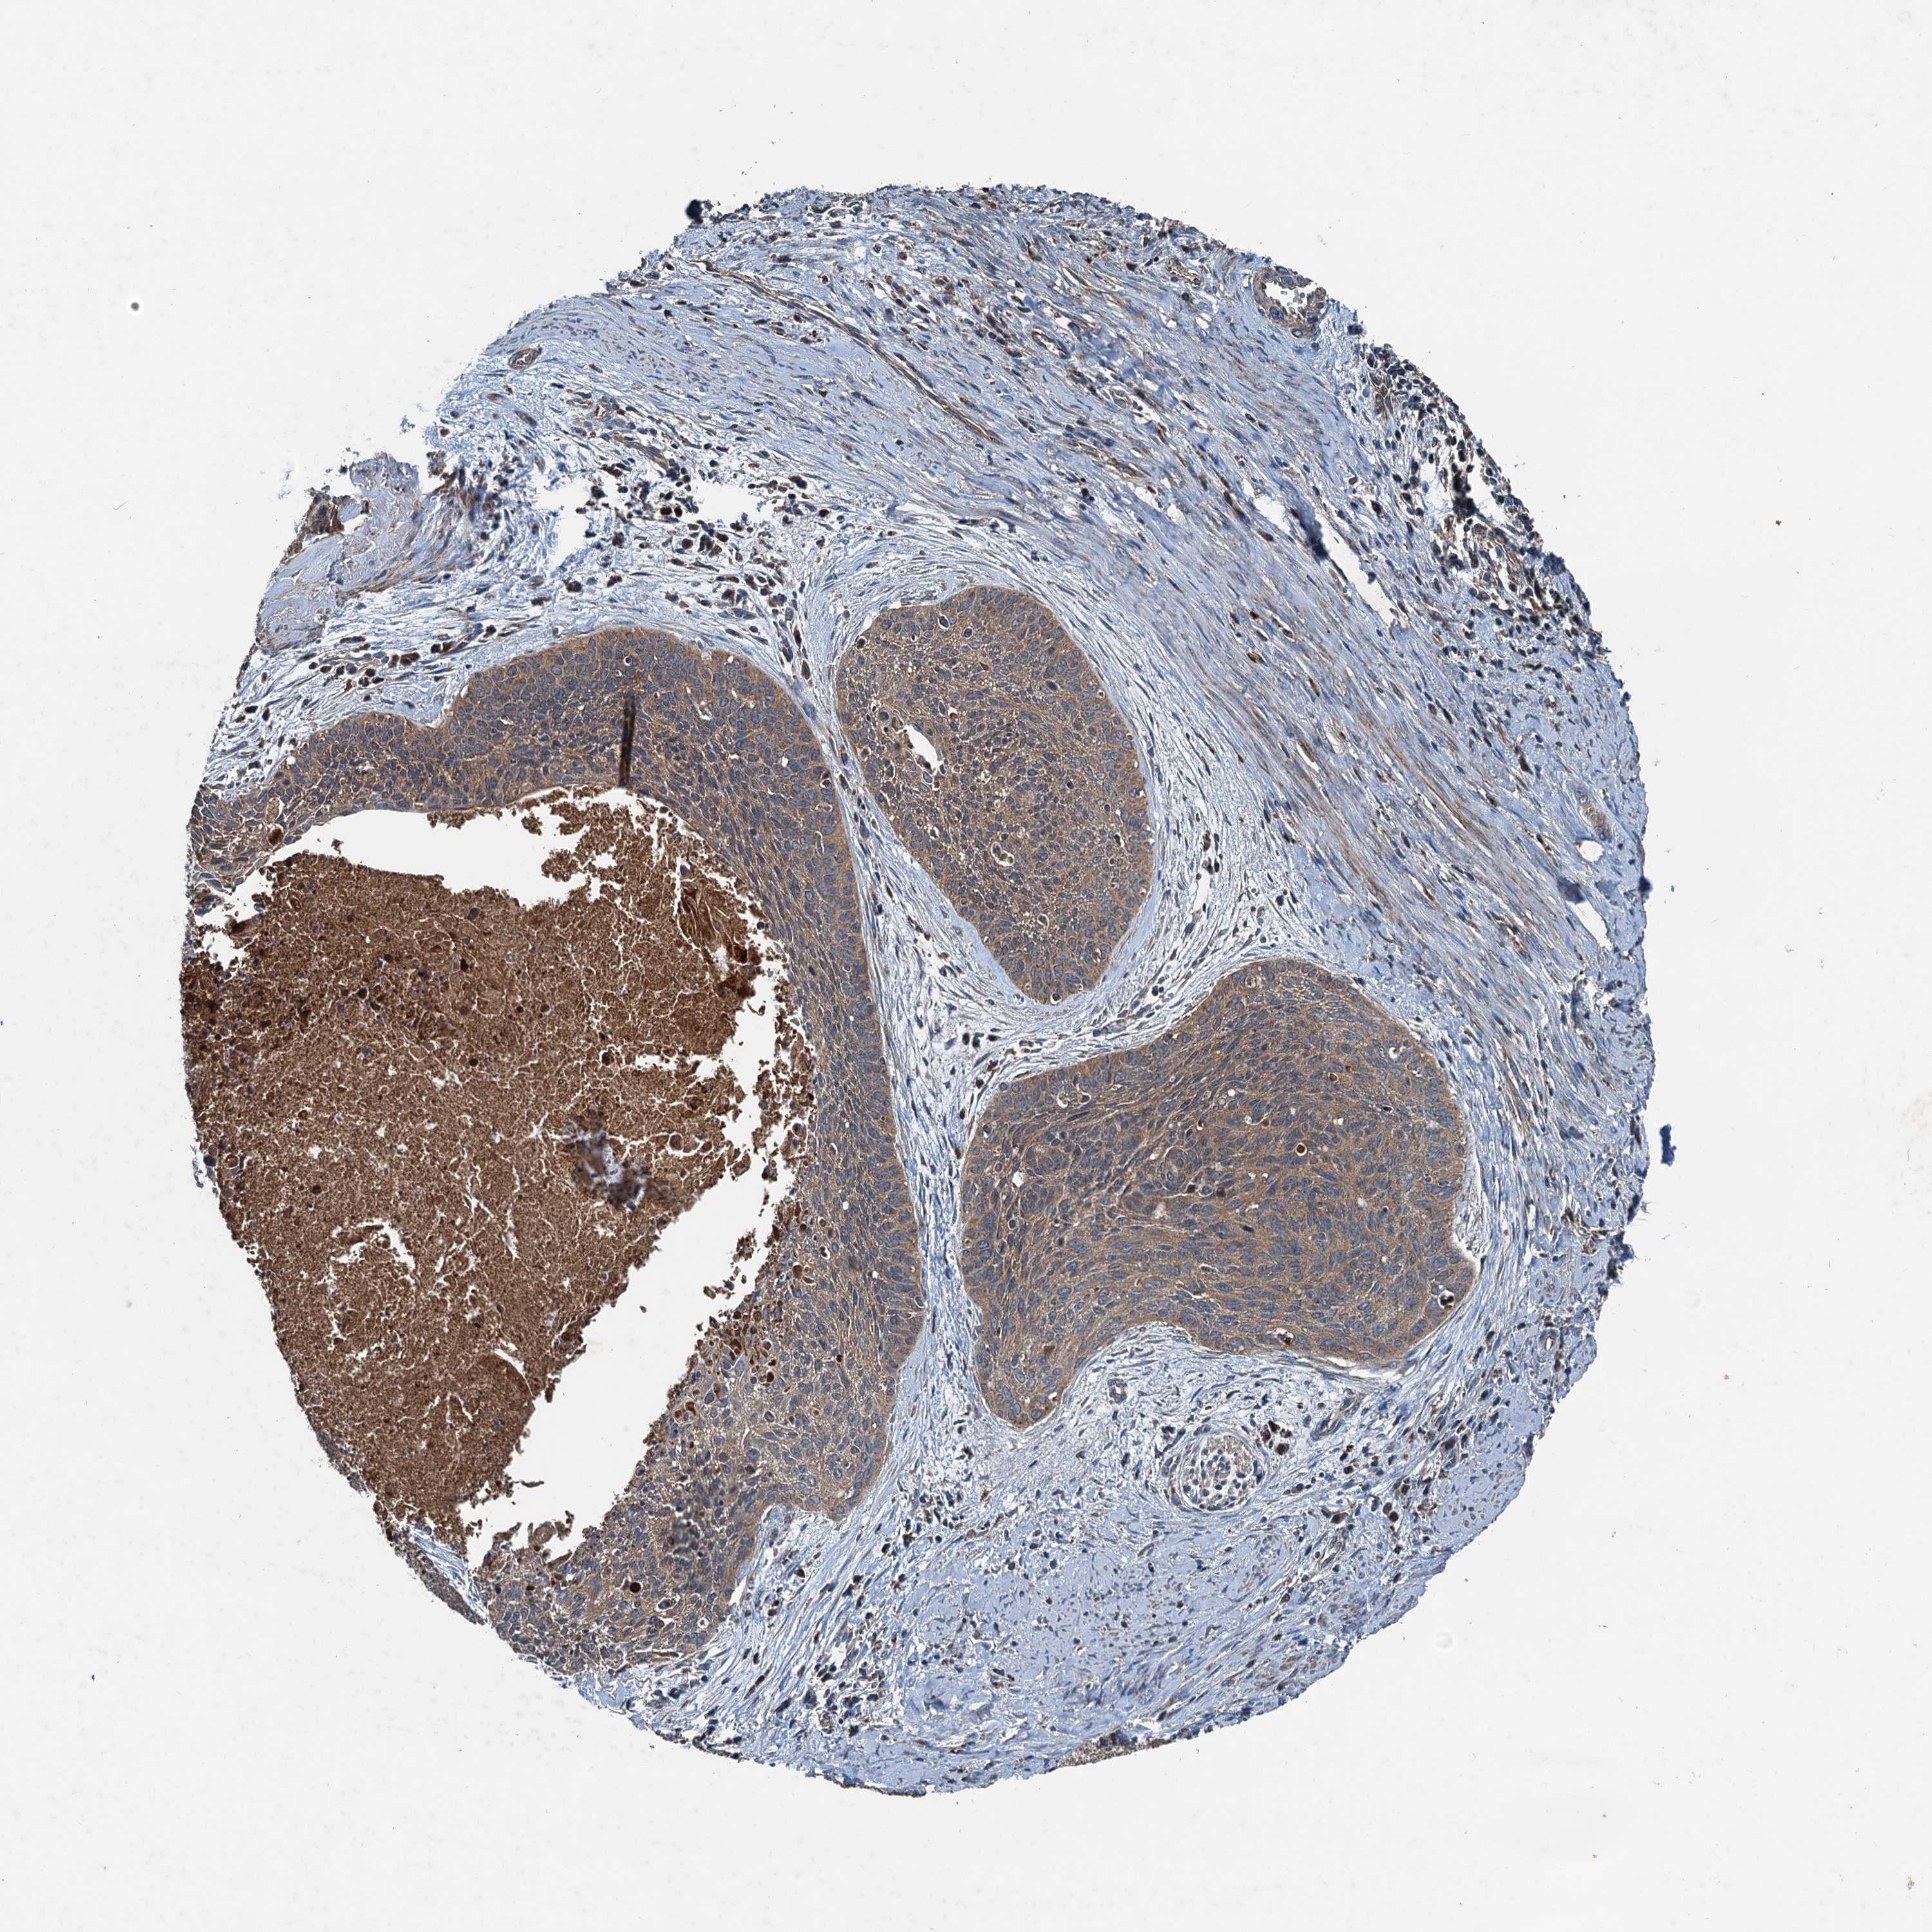

CERVICAL CANCER - Protein expressioni

A mouse-over function shows sample information and annotation data. Click on an image to view it in a full screen mode. Samples can be filtered based on level of antibody staining by selecting one or several of the following categories: high, medium, low and not detected. The assay and annotation is described here.

Note that samples used for immunohistochemistry by the Human Protein Atlas do not correspond to samples in the TCGA dataset.

Antibody stainingi

Antibody staining in the annotated cell types in the current human tissue is reported as not detected, low, medium, or high, based on conventional immunohistochemistry profiling in selected tissues. This score is based on the combination of the staining intensity and fraction of stained cells.

Each image is clickable and will lead to virtual microscopy that enables deeper exploration of all samples and also displays staining intensity scores, fraction scores and subcellular localization as well as patient and tissue information for each sample.

Antibody HPA041227

Staining

High

Medium

Low

Not detected

Intensity

Strong

Moderate

Weak

Negative

Quantity

>75%

75%-25%

<25%

None

Location

Nuclear

Cytoplasmic/membranous

Cytoplasmic/membranous,nuclear

Squamous cell carcinoma, NOS

Adenocarcinoma, NOS